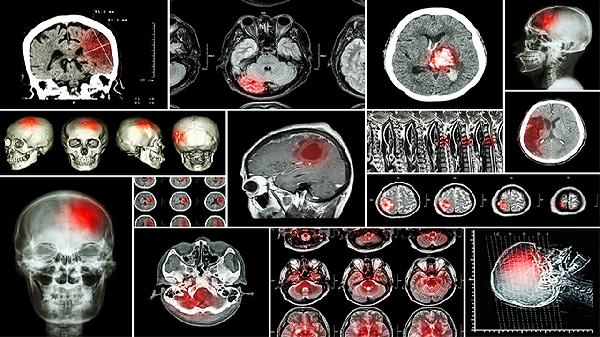

开颅手术颅骨会愈合吗 正确处理促进颅骨愈合

开颅手术后颅骨通常可以愈合,但需正确处理以促进愈合过程。开颅手术后的颅骨愈合主要与手术方式、术后护理、营养支持等因素有关,建议患者严格遵循医嘱进行康复管理。